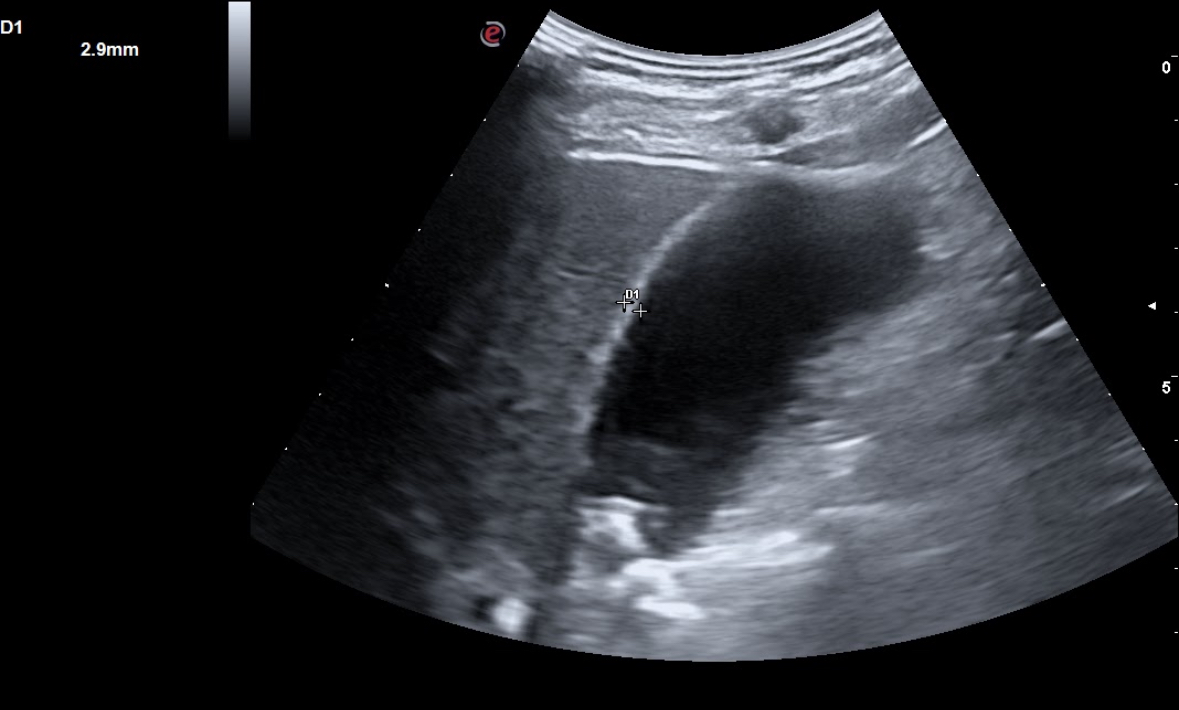

En la radiografía solicitada se aprecia una zona hiperdensa en zona de vesícula, por lo cual realizamos ecografía clínica abdominal en la que se aprecia hígado con ligera hiperecogenicidad difusa homogénea, con tamaño normal, vesícula replecionada con 3-4 imágenes hiperecoicas con sombra acústica posterior, la mayor de 1,2 cm, con una pared de 0,2 mm. Páncreas no visible en ecografía por gas. Vía urinaria normal.